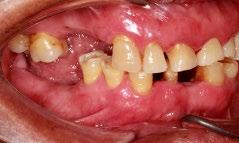

Se reporta el caso de un paciente masculino de 74 años, con antecedentes de extracciones por caries, que acude a consulta por incomodidad al comer. Fue remitido al Centro Educativo Multidisciplinario de Rehabilitación Oral, Tarímbaro, Michoacán, en octubre de 2022. Al examen clínico se encontró cálculo dental generalizado, gingivitis localizada, movilidad dental, atrición en el sector anterosuperior e inferior, ausencia de piezas posteroinferiores y superiores, y alteración de la DVO. El análisis de fotografías clínicas intraorales mostró extrusión de raíces de piezas antagonistas en las zonas edéntulas,

oclusión borde a borde y retracción gingival (Figura 1). En los estudios imagenológicos se observó ensanchamiento del ligamento periodontal y caries (Figura 2).

Figura 1. Fotografías clínicas intraorales oclusales, perfil derecho, frontales iniciales y radiografía panorámica en las que se observa caries, extrusión de piezas y ensanchamiento del ligamento periodontal.